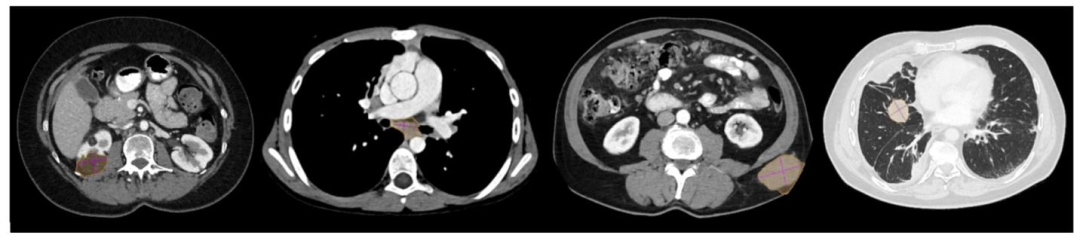

Fig. 2. Examples of GrabCut pseudo-masks. From left to right, a kidney lesion, mediastinal lymph node, subcutaneous mass, and lung lesion. Note how GrabCut tends to oversegment(orange mask ■) into healthy tissues compared to the reference measurements (purple lines ■). Lung lesions are visualized using Window Level: −500 HU, Window Width: 1400HU. Lesions outside the lungs with WL: 350 WW: 40.

图2. GrabCut伪掩码示例 从左至右依次为肾脏病变、纵隔淋巴结、皮下肿块和肺部病变。请注意,与参考测量值(紫色线条■)相比,GrabCut倾向于将健康组织过度分割(橙色掩码■)。肺部病变采用窗宽窗位:-500 HU(窗位),1400 HU(窗宽)显示,肺部外病变则使用350(窗位)/400(窗宽)。